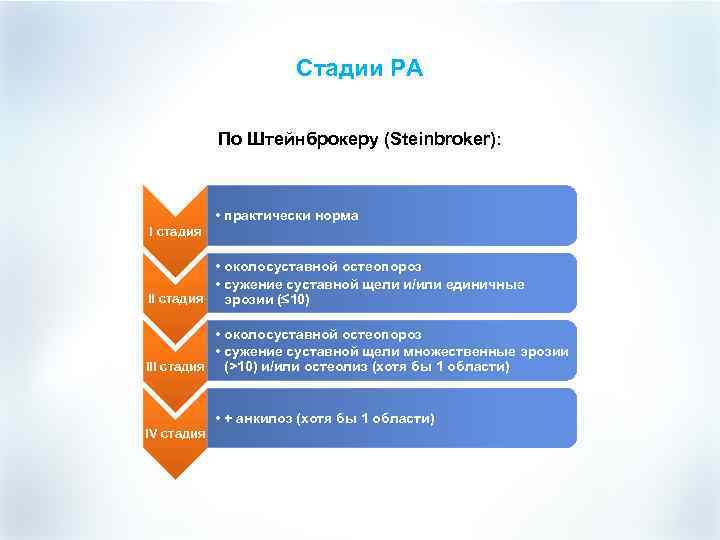

Стадии РА По Штейнброкеру (Steinbroker): • практически норма I стадия • околосуставной остеопороз • сужение суставной щели и/или единичные II стадия эрозии ( 10) • околосуставной остеопороз • сужение суставной щели множественные эрозии III стадия (>10) и/или остеолиз (хотя бы 1 области) • + анкилоз (хотя бы 1 области) IV стадия

Стадии РА По Штейнброкеру (Steinbroker): • практически норма I стадия • околосуставной остеопороз • сужение суставной щели и/или единичные II стадия эрозии ( 10) • околосуставной остеопороз • сужение суставной щели множественные эрозии III стадия (>10) и/или остеолиз (хотя бы 1 области) • + анкилоз (хотя бы 1 области) IV стадия